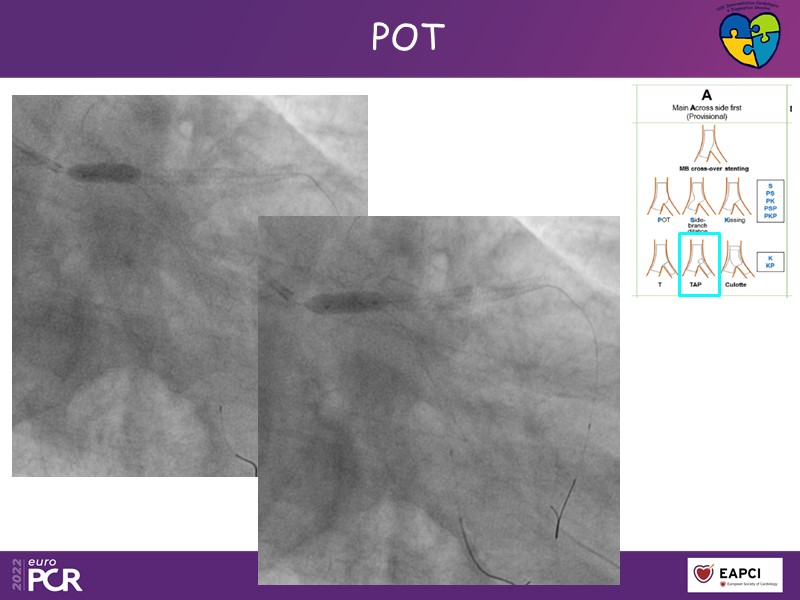

Why should the stenting strategy be adapted to side branch lesion length? How to use intracoronary imaging to improve outcomes? This session will address those questions and show you through a series of cases, examples of left main PCI from the European Bifurcation Club main trial and ROLEX registry.

- To discuss case examples of left main PCI from the European Bifurcation Club main trial and ROLEX registry

- To understand why stenting strategy should be adapted to side branch lesion length